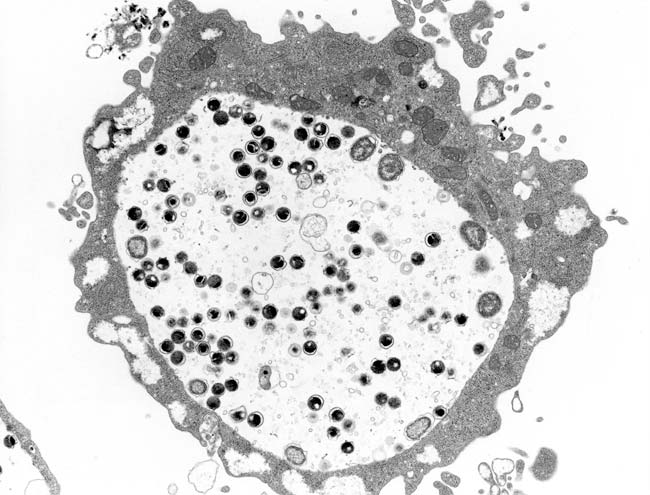

写真1.Chlamydia trachomatisの電子顕微鏡像

クラミジア・トラコマチス(Chlamydia trachomatis)が病原体で(写真1)、人工培地では増殖できない。本病原体はトラコーマの起因菌であることからこの名前がつけられたが、現在ではSTDの主要病原体として有名である。クラミジア・トラコマチスには2つの生物型(Lymphogranuloma venereum; LGV, Trachoma)がある(生物型Mouseは、最近別のクラミジア種となった)。生物型LGVは性病性リンパ肉芽腫症(鼡径リンパ肉芽腫症、第四性病ともいわれる)を起こすが、わが国では輸入例が散見されるものの、近年ほとんど発生をみない。